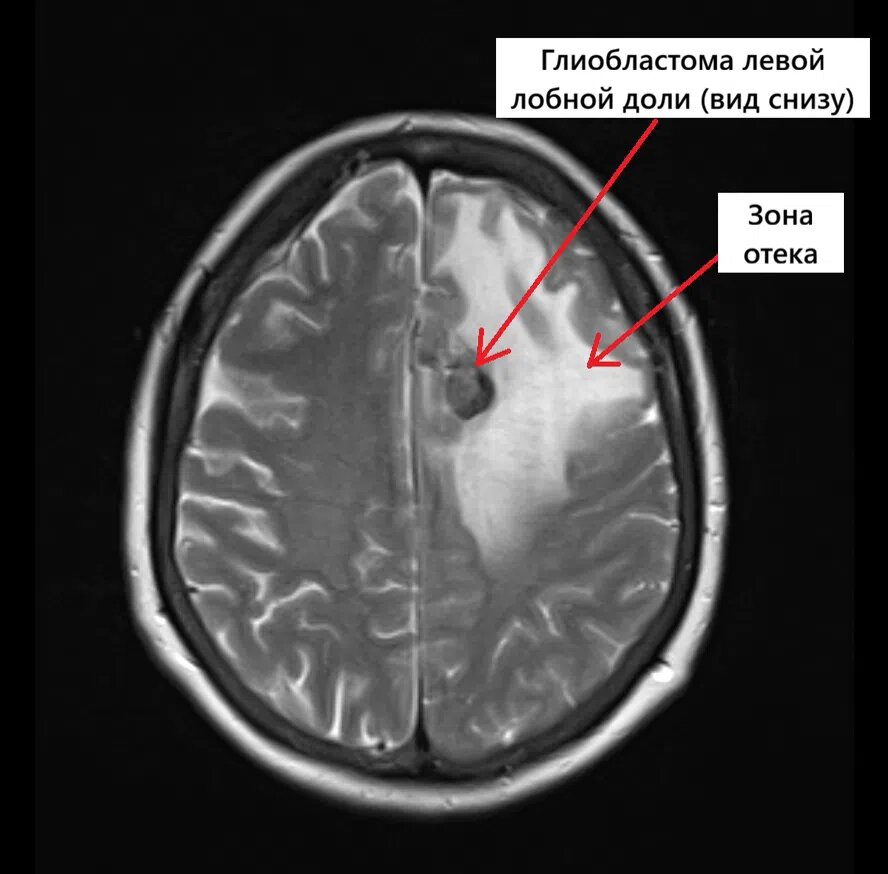

(Π Π΅Π·ΡƒΠ»ΡŒΡ‚Π°Ρ‚Ρ‹ МРВ Π½Π° Ρ„ΠΎΡ‚ΠΎ)

ΠŸΡ€ΠΈ МРВ Π³ΠΎΠ»ΠΎΠ²Π½ΠΎΠ³ΠΎ ΠΌΠΎΠ·Π³Π° Π±Ρ‹Π»ΠΎ выявлСно ΠΎΠ±ΡŠΡ‘ΠΌΠ½ΠΎΠ΅ ΠΎΠ±Ρ€Π°Π·ΠΎΠ²Π°Π½ΠΈΠ΅ Π² Π»Π΅Π²ΠΎΠΉ Π»ΠΎΠ±Π½ΠΎΠΉ Π΄ΠΎΠ»Π΅ с Π²Ρ‹Ρ€Π°ΠΆΠ΅Π½Π½Ρ‹ΠΌ ΠΎΡ‚Ρ‘ΠΊΠΎΠΌ ΠΎΠΊΡ€ΡƒΠΆΠ°ΡŽΡ‰ΠΈΡ… Ρ‚ΠΊΠ°Π½Π΅ΠΉ (Π² Π»Π΅Π²ΠΎΠΉ Π»ΠΎΠ±Π½ΠΎΠΉ Π΄ΠΎΠ»Π΅ ΠΏΠ°Ρ€Π°ΡΠ°Π³ΠΈΡ‚Ρ‚Π°Π»ΡŒΠ½ΠΎ

МРВ Π³ΠΎΠ»ΠΎΠ²Π½ΠΎΠ³ΠΎ ΠΌΠΎΠ·Π³Π° ΠΏΠ°Ρ†ΠΈΠ΅Π½Ρ‚ΠΊΠΈ с глиобластомой Π»Π΅Π²ΠΎΠΉ Π»ΠΎΠ±Π½ΠΎΠΉ Π΄ΠΎΠ»ΠΈ (Π²ΠΈΠ΄ снизу)

ΠŸΡ€ΠΈ МРВ Π³ΠΎΠ»ΠΎΠ²Π½ΠΎΠ³ΠΎ ΠΌΠΎΠ·Π³Π° Π±Ρ‹Π»ΠΎ выявлСно ΠΎΠ±ΡŠΡ‘ΠΌΠ½ΠΎΠ΅ ΠΎΠ±Ρ€Π°Π·ΠΎΠ²Π°Π½ΠΈΠ΅ Π² Π»Π΅Π²ΠΎΠΉ Π»ΠΎΠ±Π½ΠΎΠΉ Π΄ΠΎΠ»Π΅ с Π²Ρ‹Ρ€Π°ΠΆΠ΅Π½Π½Ρ‹ΠΌ ΠΎΡ‚Ρ‘ΠΊΠΎΠΌ ΠΎΠΊΡ€ΡƒΠΆΠ°ΡŽΡ‰ΠΈΡ… Ρ‚ΠΊΠ°Π½Π΅ΠΉ (Π² Π»Π΅Π²ΠΎΠΉ Π»ΠΎΠ±Π½ΠΎΠΉ Π΄ΠΎΠ»Π΅ ΠΏΠ°Ρ€Π°ΡΠ°Π³ΠΈΡ‚Ρ‚Π°Π»ΡŒΠ½ΠΎ опрСдСляСтся патологичСскоС ΠΎΠ±Ρ€Π°Π·ΠΎΠ²Π°Π½ΠΈΠ΅ Π½Π΅ΠΏΡ€Π°Π²ΠΈΠ»ΡŒΠ½ΠΎΠΉ Ρ„ΠΎΡ€ΠΌΡ‹, с нСсколько Π½Π΅Ρ‡Π΅Ρ‚ΠΊΠΈΠΌΠΈ Π½Π΅Ρ€ΠΎΠ²Π½Ρ‹ΠΌΠΈ бугристыми ΠΊΠΎΠ½Ρ‚ΡƒΡ€Π°ΠΌΠΈ, Ρ€Π°Π·ΠΌΠ΅Ρ€ΠΎΠΌ 26Ρ…18Ρ…32 ΠΌΠΌ, с Π²Ρ‹Ρ€Π°ΠΆΠ΅Π½Π½Ρ‹ΠΌ ΠΎΠ±ΡˆΠΈΡ€Π½Ρ‹ΠΌ ΠΏΠ΅Ρ€ΠΈΡ„ΠΎΠΊΠ°Π»ΡŒΠ½Ρ‹ΠΌ ΠΎΡ‚Π΅ΠΊΠΎΠΌ, Ρ€Π°ΡΠΏΡ€ΠΎΡΡ‚Ρ€Π°Π½ΡΡŽΡ‰ΠΈΠΌΡΡ Π½Π° Π»ΠΎΠ±Π½ΡƒΡŽ ΠΈ Ρ‚Π΅ΠΌΠ΅Π½Π½ΡƒΡŽ Π΄ΠΎΠ»ΠΈ, Ρ€Π°Π·ΠΌΠ΅Ρ€ ΠΎΡ‚Π΅ΠΊΠ° 116Ρ…46Ρ…55 ΠΌΠΌ. Π’ височной Π΄ΠΎΠ»Π΅ Π·ΠΎΠ½Π° ΠΎΡ‚Π΅ΠΊΠ° Π±Π΅Π»ΠΎΠ³ΠΎ вСщСства 31Ρ…23 ΠΌΠΌ.)Β